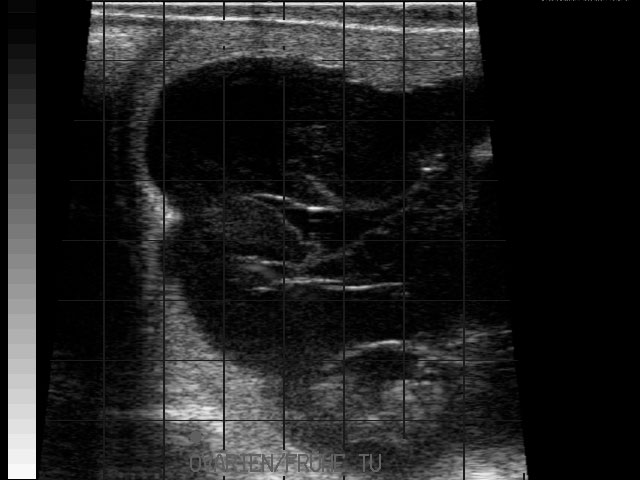

Eierstockstumor